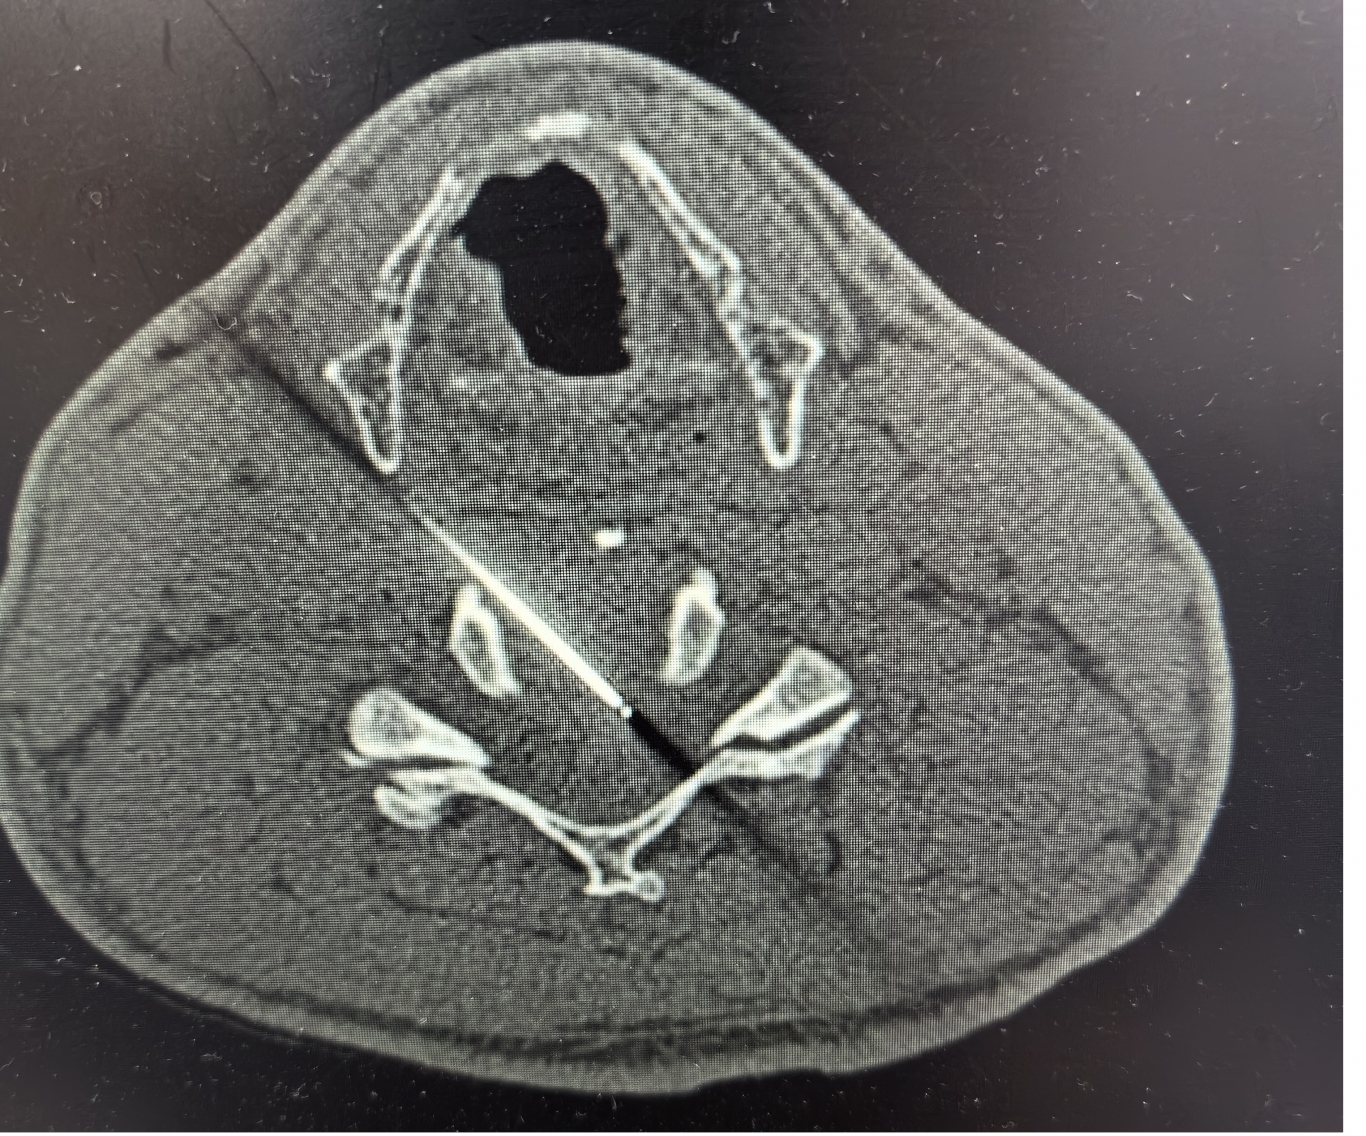

手术之后3天,黄大伯疼痛得到很好缓解,露出了许久没有的笑容,终于可以安心躺着睡觉了,1个月后基本恢复了正常生活,6个月后复查CT发现突出的颈椎间盘已经基本消失了,黄大伯一家人对治疗效果非常满意。

手术之前CT,巨大突出物 术后6个月复查CT:突出物消失